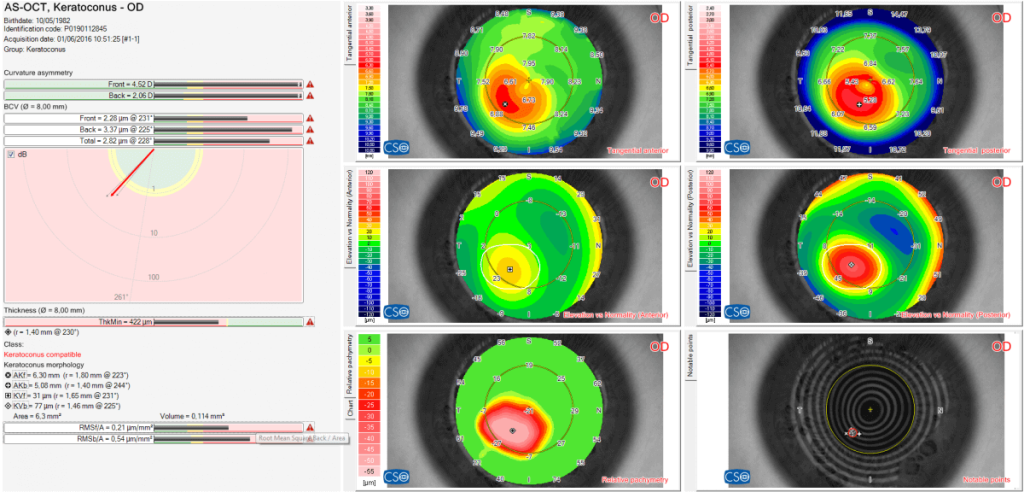

KERATOCONOUS SCREENING

Keratoconous screening provides the clinician with important information about the patinets cornea. Understanding this can help prevent complications associated with ectasia before corneal surgery is undertaken.